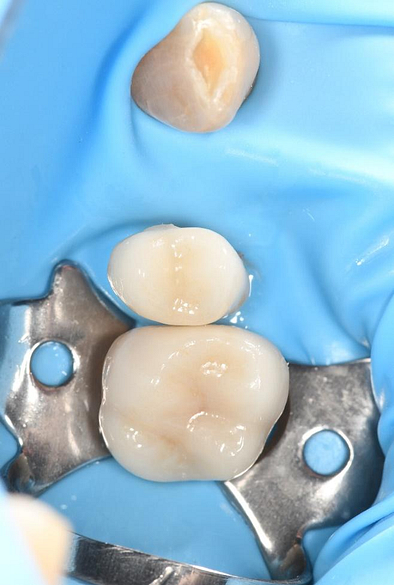

His previous dentist retired, and the patient visited me for the first time as an emergency visit due to symptomatic irreversible pulpitis from a cracked tooth (46). Root canal treatment on tooth 46 was completed, and a crown placed.

Digital impressions were captured using the TRIOS 4 intraoral scanner, and the implant-supported crown was designed using 3Shape Design Studio.

The crown was milled from a high-strength, multilayered zirconia and hand-finished to achieve a lifelike appearance.

At the final appointment, the crown was securely attached to the implant, resulting in a beautiful, natural-looking restoration.